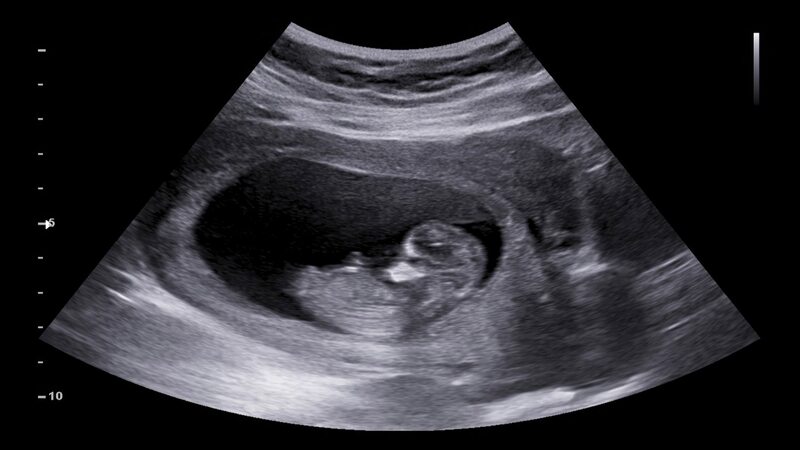

During the 8th to 9th week of pregnancy, the genital tubercle starts growing and taking form. But the shapes look very similar until the 14 weeks. But, the 12th-week ultrasound helps to predict the further growth of the tubercle.

The Nub theory explains that if you can get a good look at the nub, you can determine how it will grow out in the upcoming ways. The angle of the nub in connection with the spinal cord can help you determine if the nub will grow out into a penis or Clitoris.

Yes. You can predict the sex of the baby using the Nub Theory. For this, you need to find a clear picture of the nub to make the spine visible horizontally. You can check the nub or any small protrusion where your baby`s legs will form horizontal vision.

If your baby’s nub is inclined at 30 degrees to its spine, it indicates that you will have a boy baby. But how will someone measure the 30 degrees? To determine this, take your ultrasound and draw a straight line along the spine or where the butt is; you can identify the direction of the nub.

If the nub is pointing up away from the straight line, it is a boy. If the nub is pointing downwards, it indicates a girl.